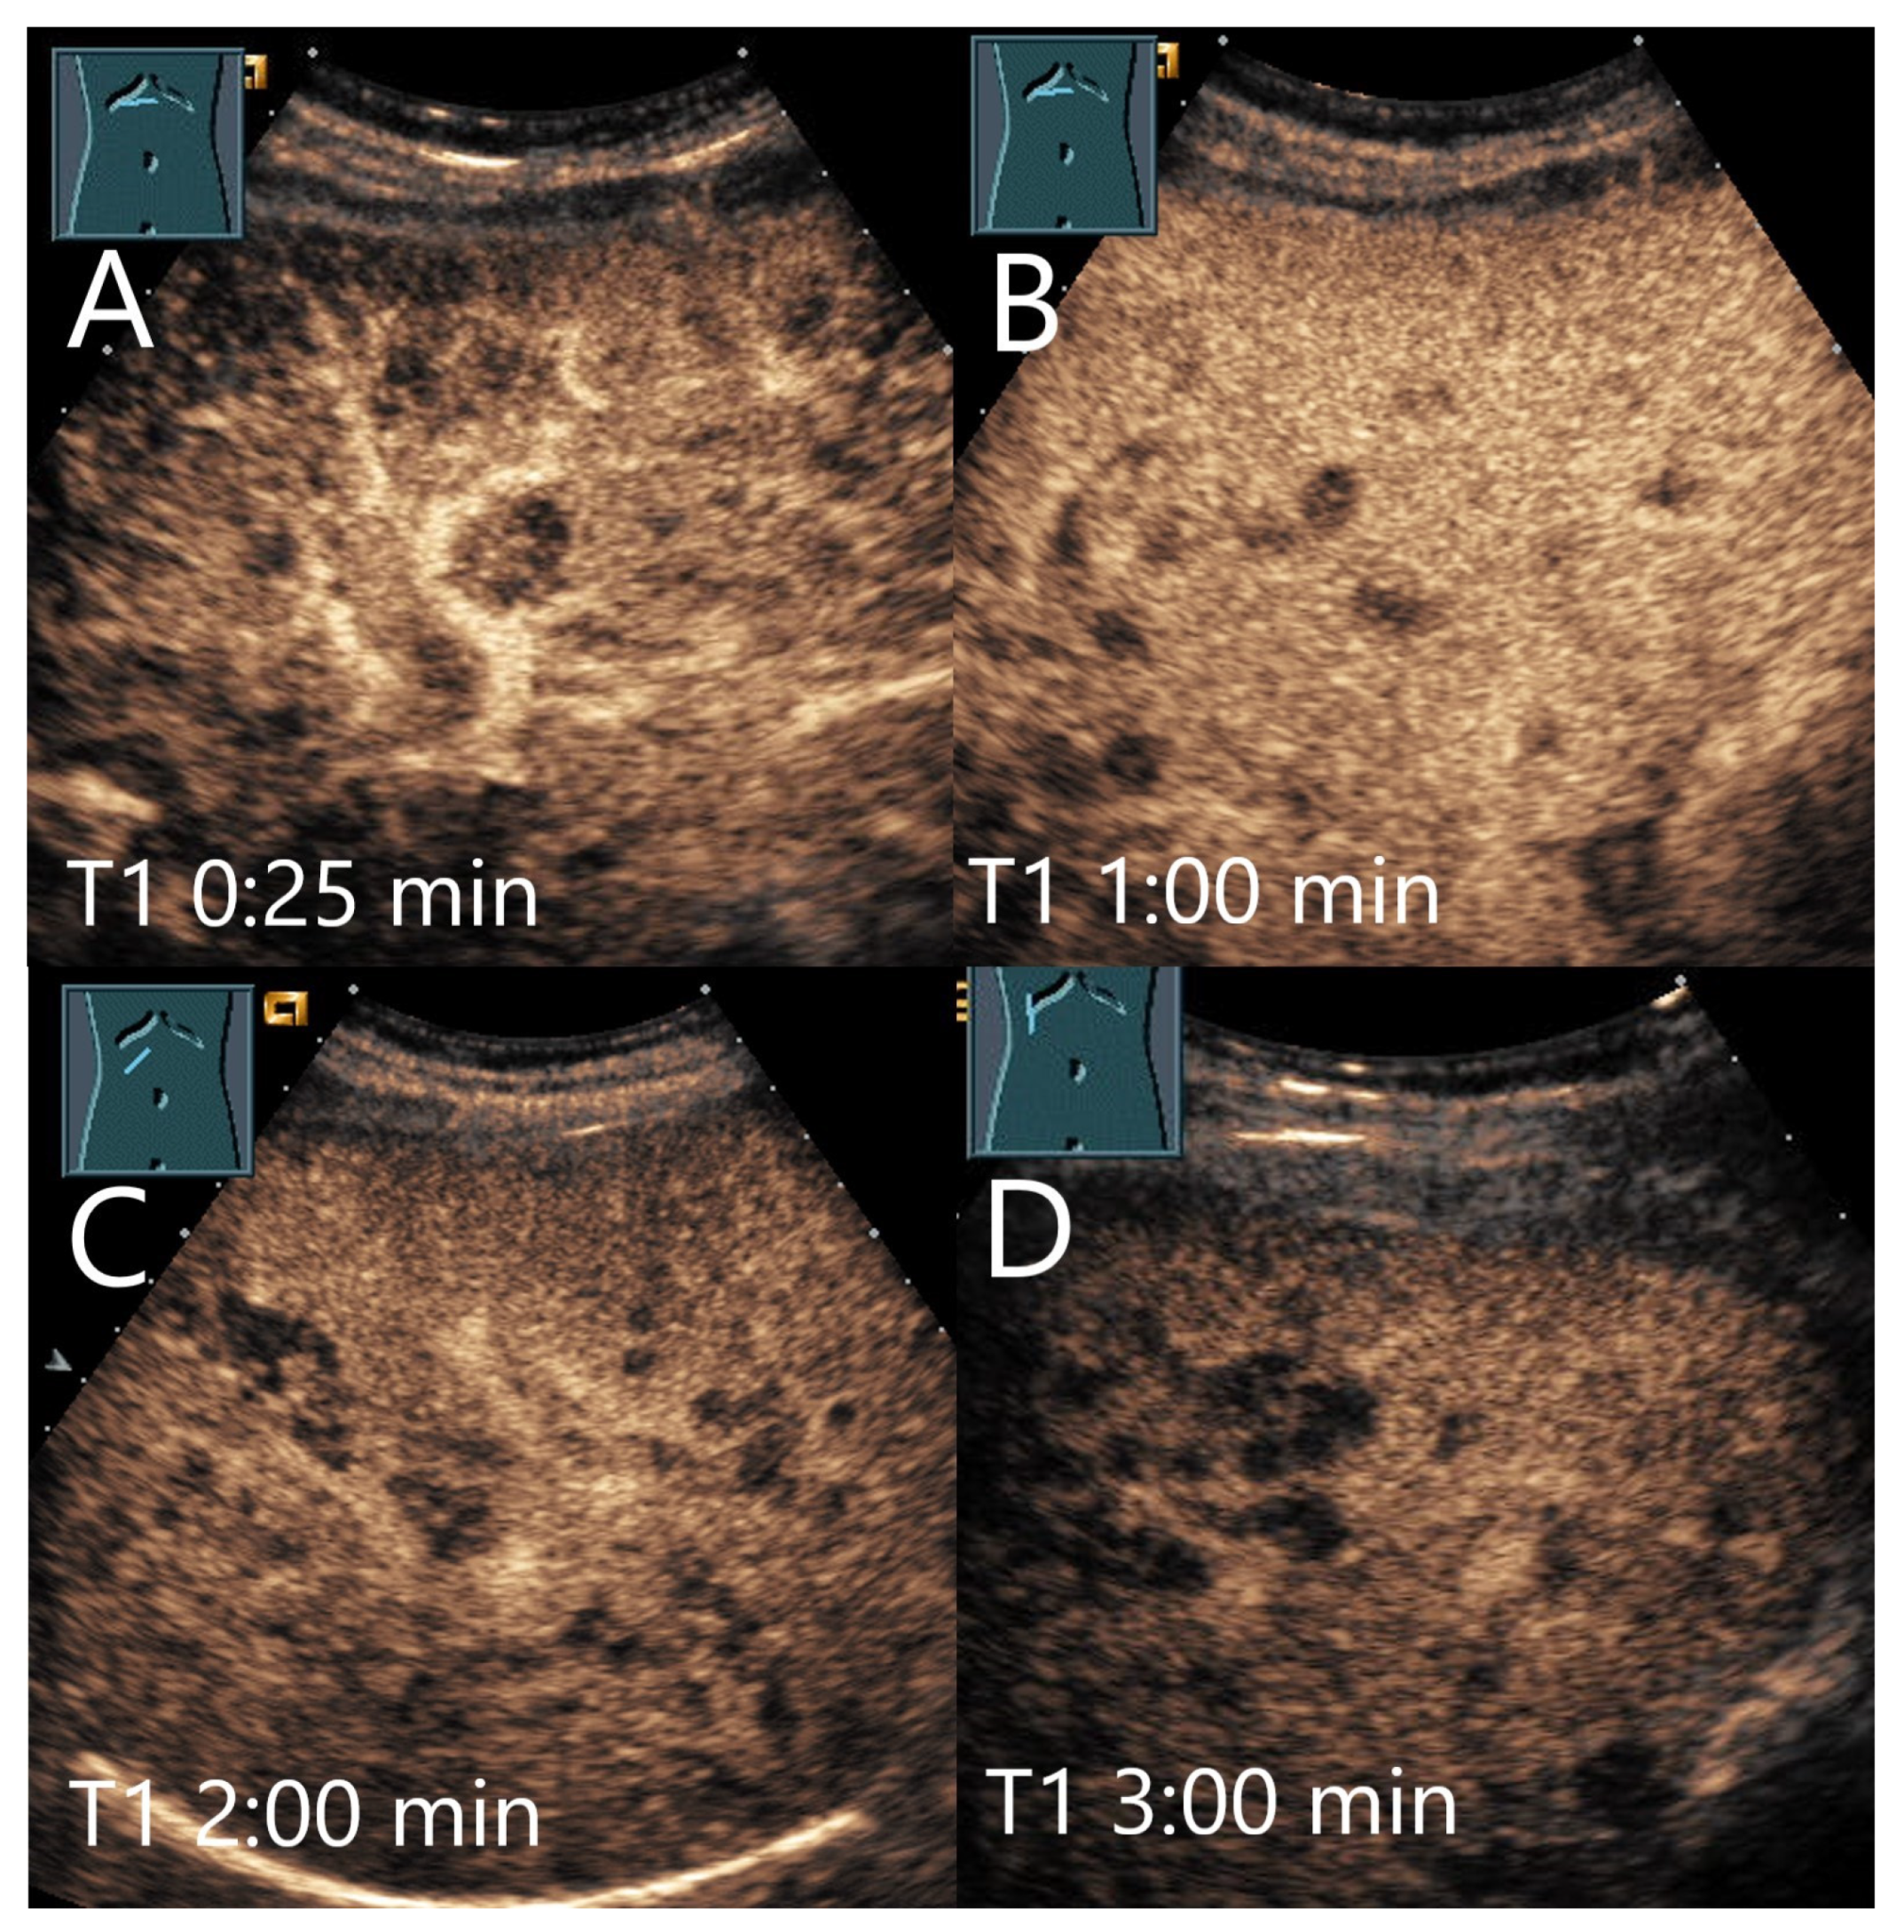

| FNH | Isoechoic, hypoechoic, sometimes hypoechoic rim. | Wheel spoke pattern, central artery, rarely peripheral artery and wheel. spoke pattern. Centrifugal filling | Hyperenhancement to isoenhanced, central scare. | Fibrosis and vascular obliteration. |